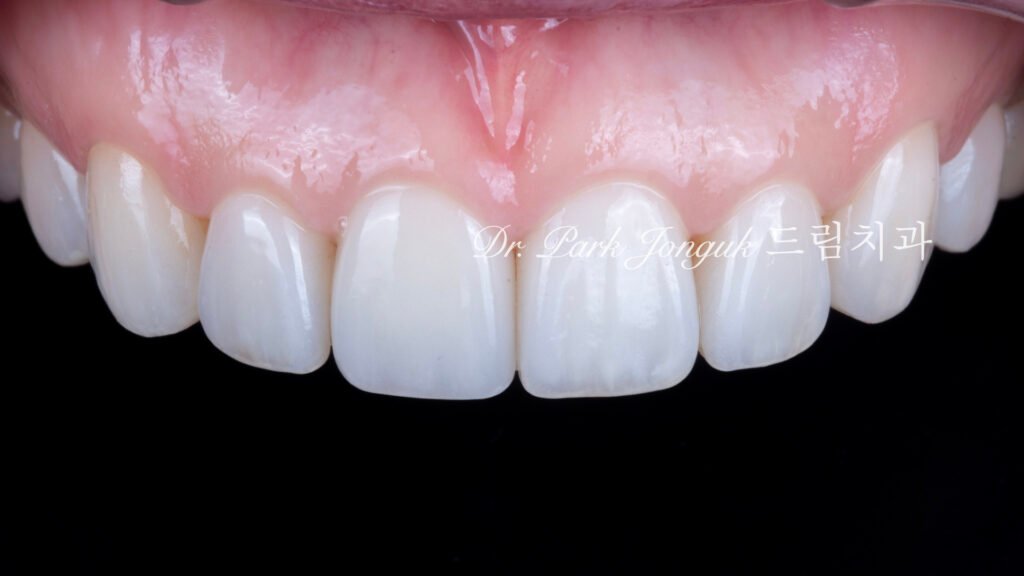

사진 9. 완성된 라미네이트

두께는 얇지만 강도와 색 안정성이 뛰어나고,

자연스러운 투명감과 질감이 살아 있음.

사진 10~12. 치료 후 결과

치아는 커지지 않았지만 형태와 색, 투명감이 완벽히 조화됨.

교정으로 부족했던 입체감이 복원되며

환자 본인도 “이제서야 진짜 완성된 느낌이에요.”라고 만족하셨습니다.